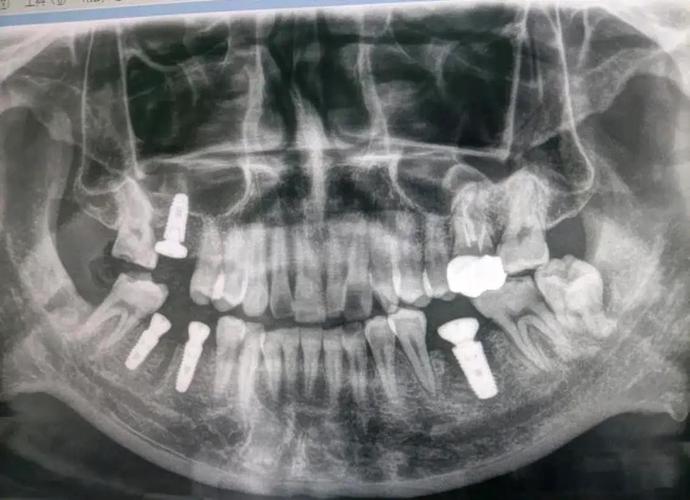

(1)口腔全景片(曲面断层片,Panoramic Radiography, PANO)

- 原理:通过X线球管和胶片同步旋转,一次性拍摄全口牙齿、牙槽骨、颌骨及周围结构的二维影像。

- 优势:视野广,可观察全口牙列、牙槽骨整体情况,操作简单、辐射剂量低(约0.007mSv,相当于1/10次胸片),价格便宜(约100-200元)。

- 局限性:二维成像,存在影像重叠(如上下牙槽骨重叠),无法精确测量骨厚度、密度,对细微骨缺损或神经管位置的判断准确性有限。

- 适用场景:初步筛查、简单牙列缺损(如单颗后牙缺失,骨量充足)、无复杂病史(如无上颌窦炎、无颌骨手术史)的患者。